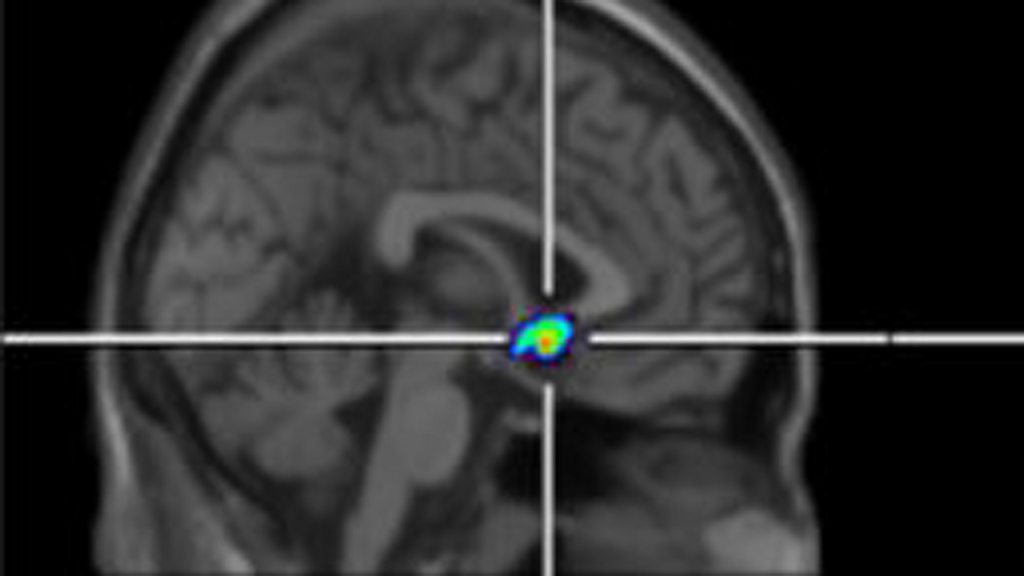

Chronic pain, pain that lasts for more than six months or so, is a huge problem. It affects at least ten per cent of the world’s population; about 60 million people. The treatment options range from drugs to cognitive behavioural therapy, but are fairly limited, and scientists are trying to find out more about the chemical conversations going on in our brains which control how we feel pain. They have known for a while that we have receptors in our brain, like tiny docking stations, that link up with natural painkilling opiates like endorphins to reduce pain. But now for the first time, researchers have shown that the numbers of these opiate receptors seem to increase in response to pain, naturally increasing our pain thresholds and helping people with chronic pain cope better. Anthony Jones is professor of neuro-rheumatology at the University of Manchester, and his research has just been published in the journal Pain. Maternal health Sierra Leone Sierra Leone has amongst the worst rates of maternal mortality in the world. In the last five years, the government has been tackling the problem head on by providing better care for pregnant and breastfeeding women. Maternal healthcare was improving, but then the Ebola crisis struck. A report from the World Bank estimates that more than 4,000 extra women a year across Guinea, Liberia and Sierra Leone could die from complications during pregnancy and child birth, because of the devastating effect of Ebola on already fragile health systems. The BBC’s Kati Whitaker reports from Sierra Leone. Film & health Film is powerful and is something that a group of health advocates, doctors, patients and film-makers want to tap into more to spread public health messages. They believe that film is the ideal medium to communicate stories, to inspire and encourage people about their health; even address health inequalities round the world. They have organised the first Global Health Film Festival, which takes place this week (October 30th and 31st 2015) at the Royal Society of Medicine in London. Dr Joseph Fitchett is a clinical research fellow at Harvard School of Public Health and a co-founder of the Global Health Film Initiative, the partnership behind the festival. Picture: Patients with chronic pain have differences in opioid receptors in a region of the brain that processes pain and motivation. Credit: Human Pain Research Group, University of Manchester